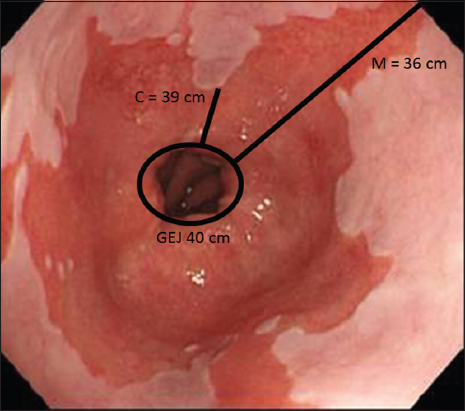

Figure 1 From Adenocarcinoma Arising From Short Segment Barrett S

Images Of A Short Segment Barrett S Esophagus Showing The